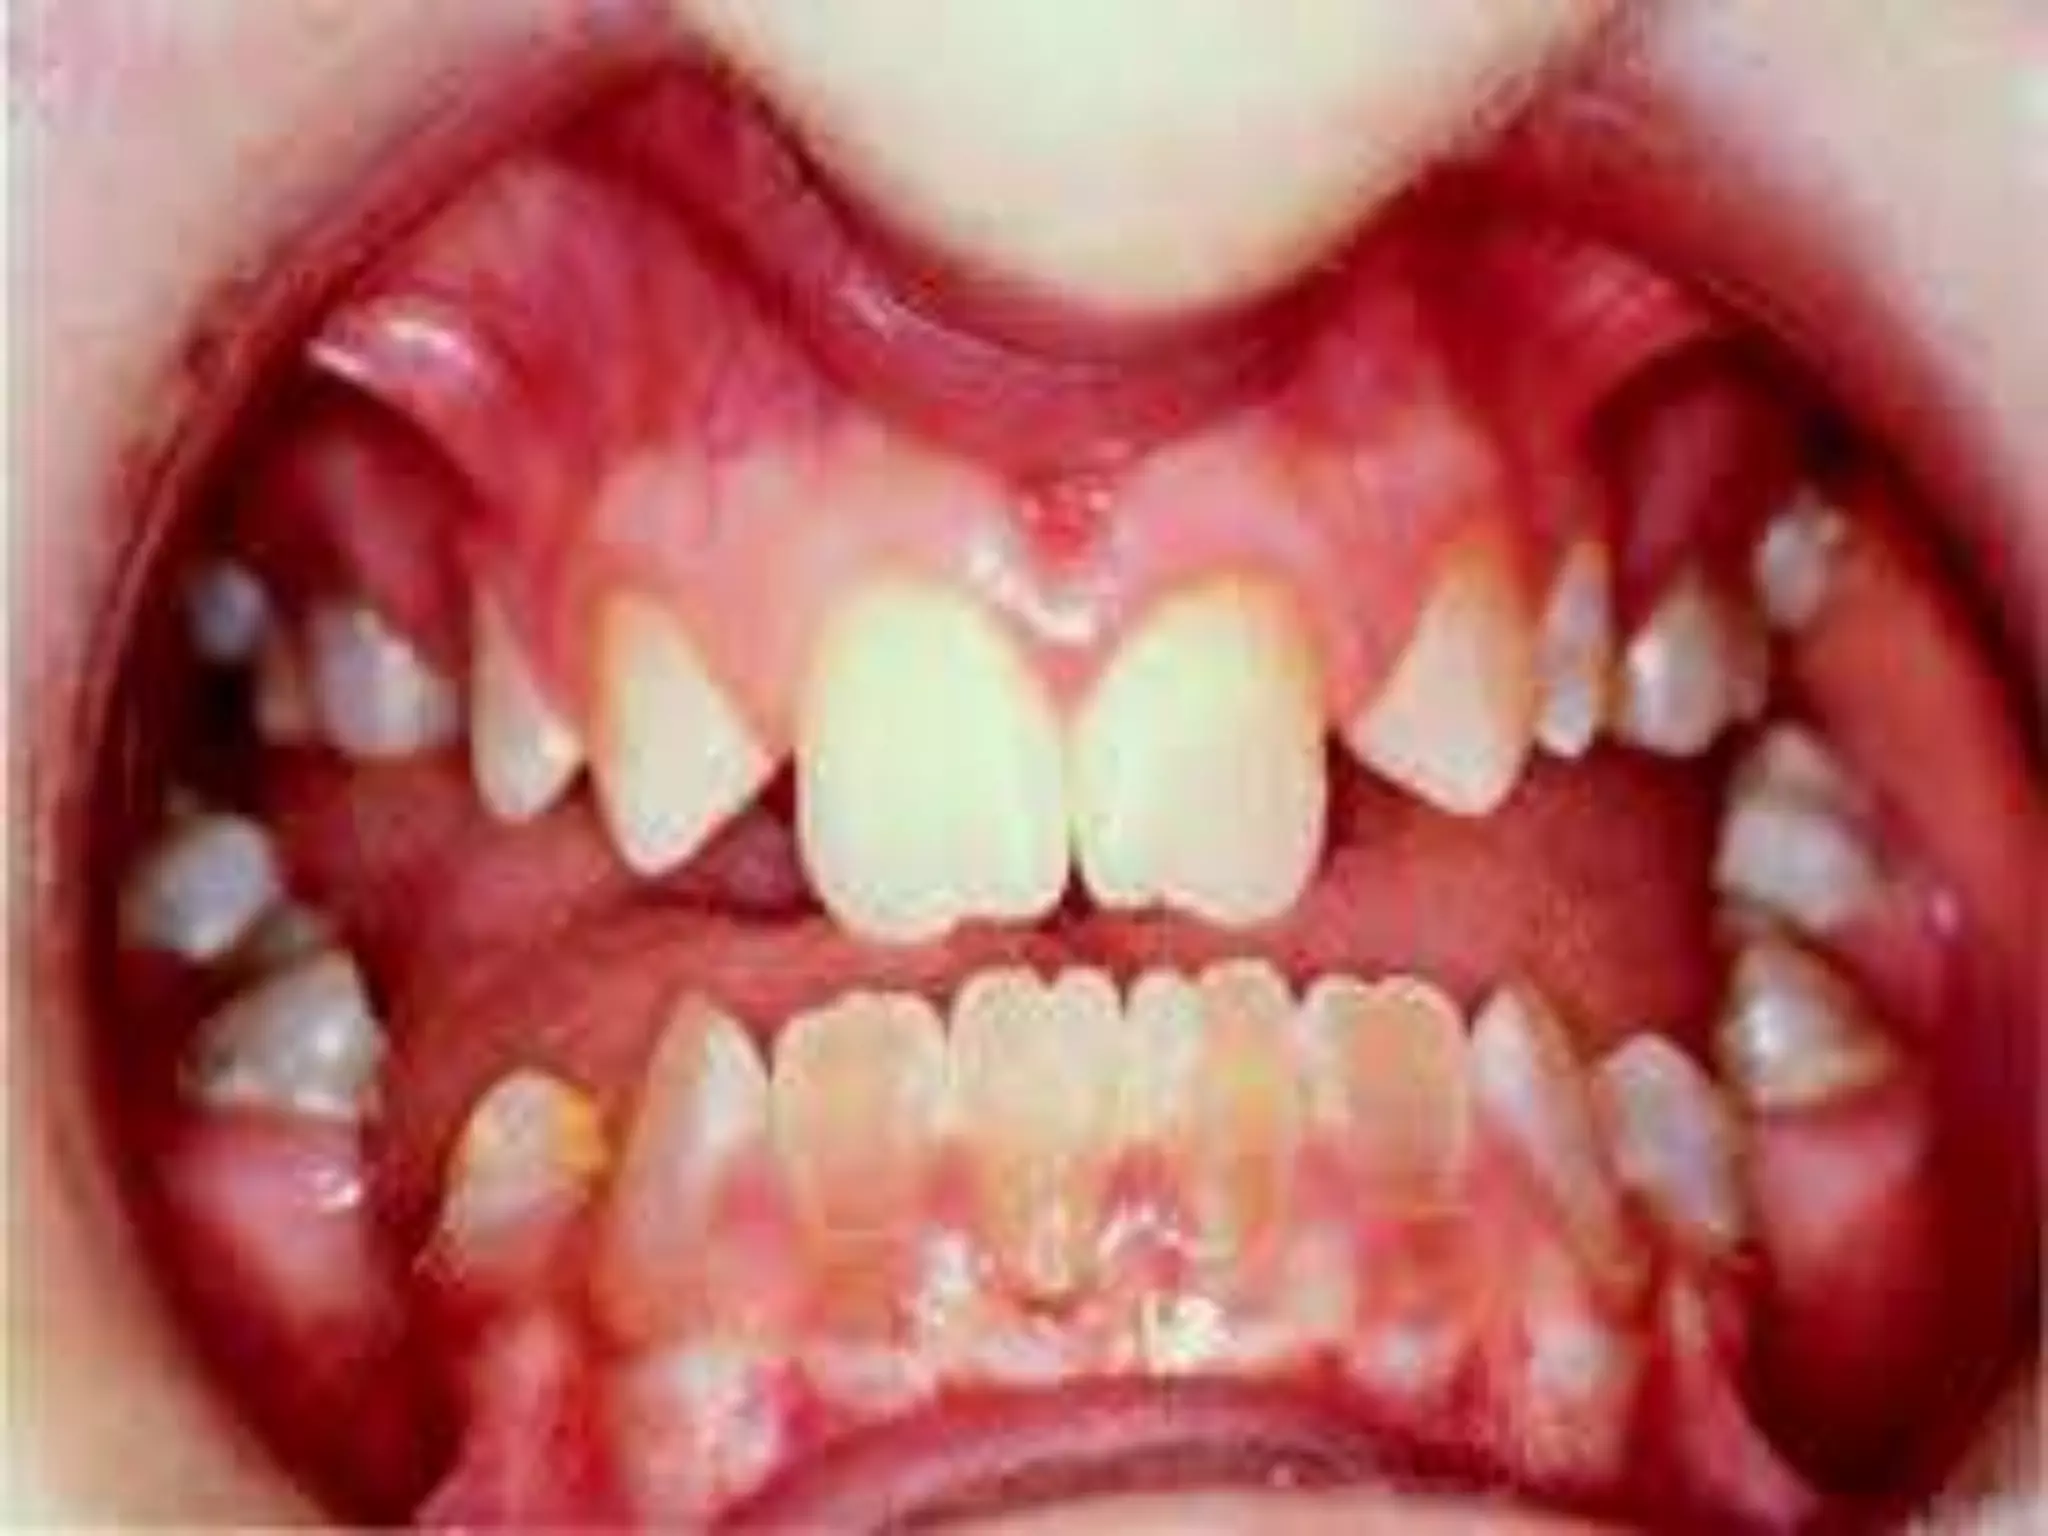

OSTEOGENESIS IMPERFECTA

(BRITTLE BONES)

Commonest genetic disorder of bone

Type 1 collagen (abnormal synthesis & structure)

Abnormalities of bones, teeth, sclerae and skin

c/f:

Osteopenia

Liability to fracture

Laxity of ligaments

Blue sclerae

Dentinogenesis imperfecta (crumbling teeth)